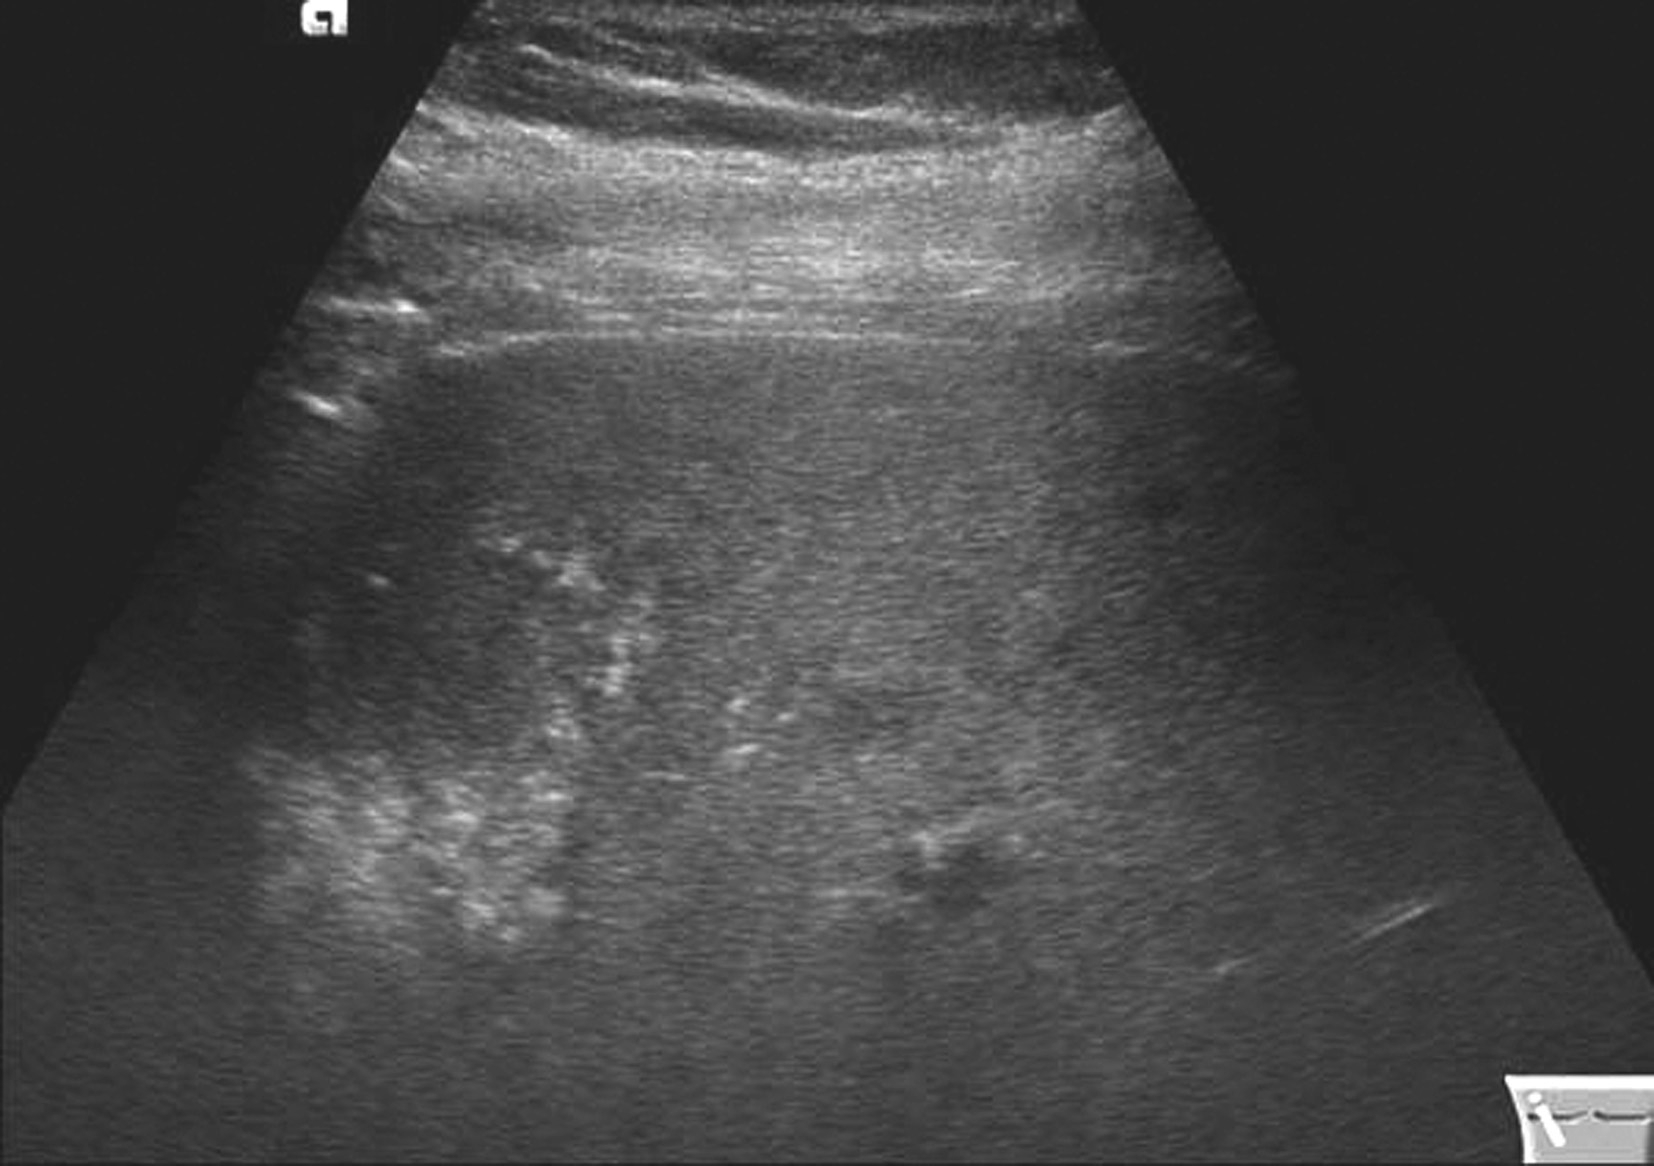

(1)灰阶超声:

①肝形态正常,轻、中度脂肪肝大小正常或增大,重度脂肪肝肝体积可增大;轻、中度脂肪肝肝实质内回声弥漫性致密增强,即所谓“明亮肝”。②前半部回声细密,由浅至深回声逐渐减弱。轻度:后半部回声稍衰减,深面肝包膜回声可见;中度:肝深面1/3回声明显减低,可呈低回声,深面肝包膜回声不显示,提高增益可显示;重度:肝深面2/3回声明显减低,深面肝包膜回声不显示。③肝内管道结构回声减弱,分支不易显示,中度和重度者血管结构显示不清。

(2)彩色多普勒超声:

重度脂肪肝患者肝内血管血流不易显示。

需要注意的是,超声图像判断脂肪肝的程度无量化标准,检查者及使用仪器不同会得出不同结论,随着仪器设备的进步,脂肪肝深面实质可无明显衰减,因此脂肪肝轻重与否需要结合患者的血脂和肝功能状况综合进行判断。

【声像图表现】

局限性脂肪肝超声像图表现如图5-21-4所示:

图5-21-4 局限性脂肪肝二维灰阶图像

也称为叶段型脂肪肝,肝实质脂肪变分布在某一肝叶或肝段,或呈斑片状或结节状,回声明显增强,境界清晰,无占位效应,肝内管道结构正常。

脂肪变的肝叶或段内血管无受压及推移,血流可正常显示。